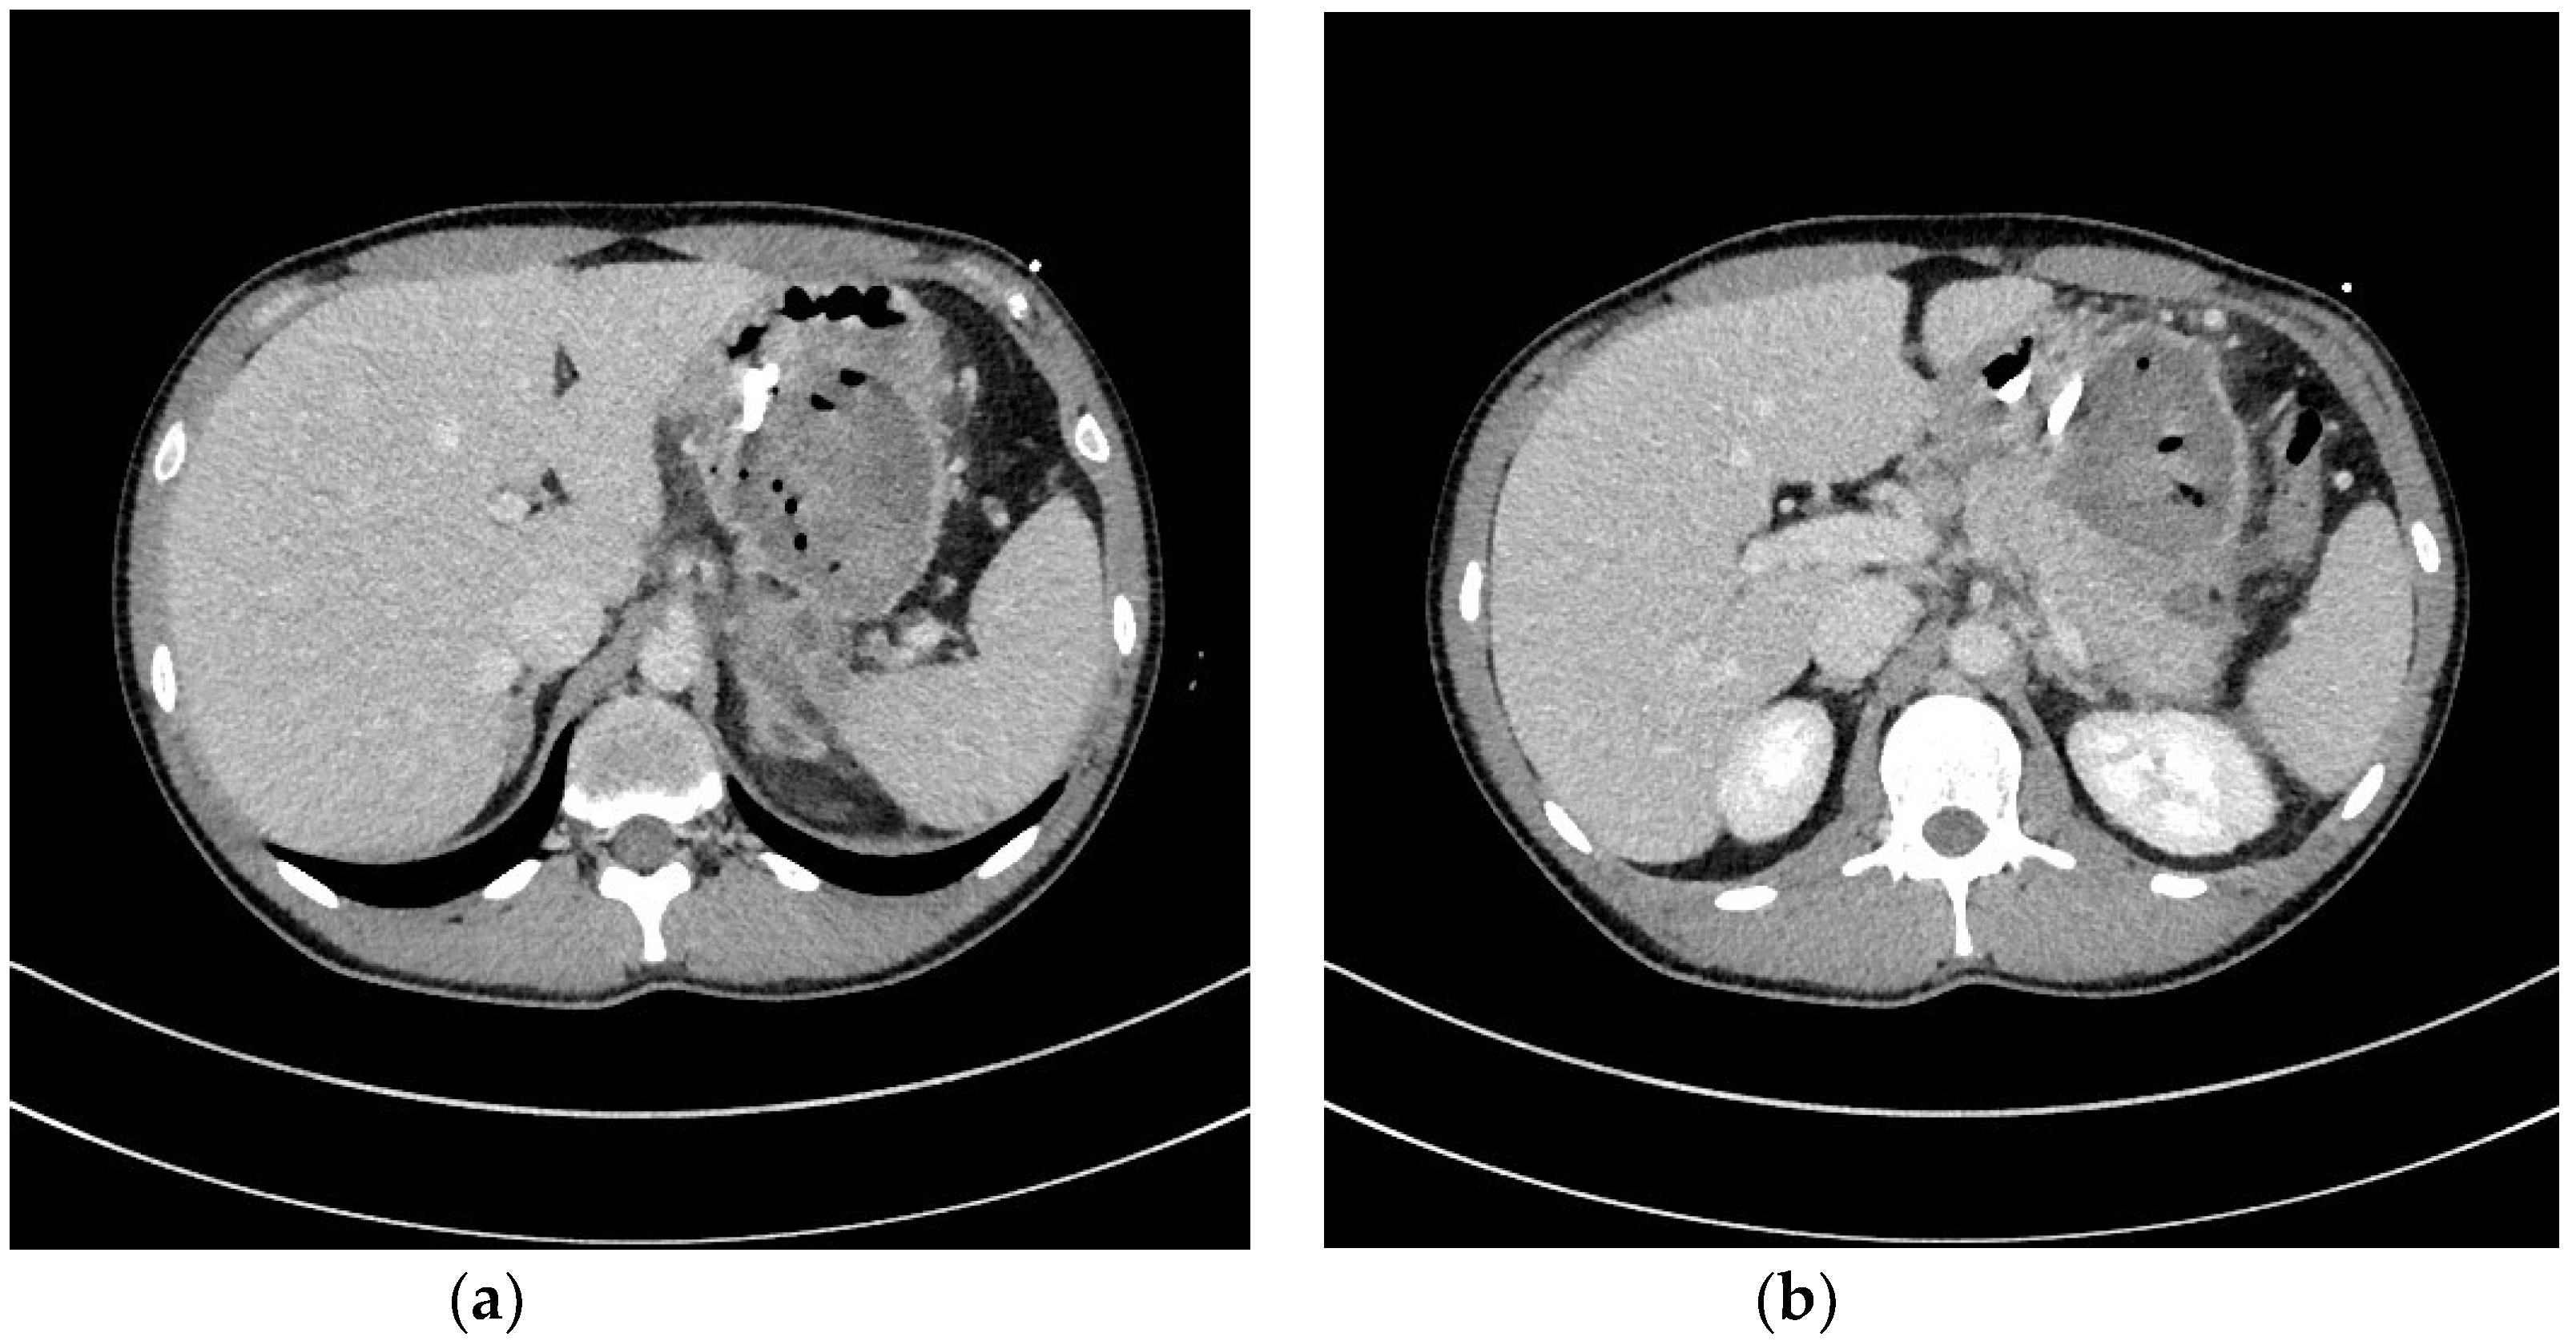

| Transmural endoscopic drainage with use of plastic stents | Active (with nasal drain) or passive (without nasal drain) transmural drainage enabled via insertion of plastic stent or stents through the transmural fistula into lumen of necrotic cavity. Mostly used in cases of well-liquefied collections of WOPN with small number of necrotic tissues in the lumen of WOPN, which usually take place after six weeks from the beginning of ANP. This type of drainage should be used in cases, where there is no necessity to perform endoscopic necrosectomy. |

| Transmural endoscopic drainage with use of SEMSs | Active (with nasal drain) or passive (without nasal drain) transmural drainage accomplished via insertion of metal stent (SEMS) through the transmural fistula into lumen of necrotic collection. Indications for this type of drainage are extensive WOPN containing poorly-liquefied necrotic tissues, in which endoscopic necrosectomy may be necessary in the next step. SEMSs are usually used in the endoscopic treatment of WOPN up to sixth week from the beginning of ANP. |